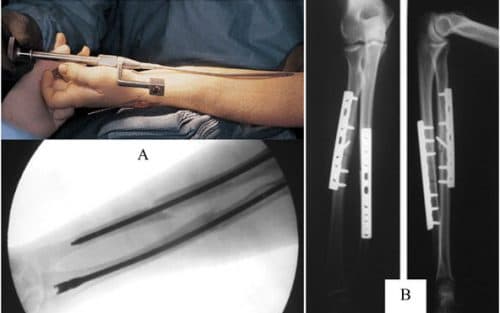

Kết xương bằng nẹp vít là phương pháp phẫu thuật xương khớp thường được áp dụng tại các bệnh viện lớn, mang lại hiệu quả cao